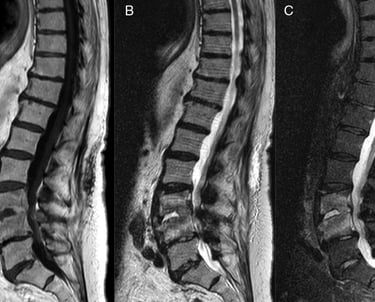

Initial assessment of bone damageMRI Scan

Best for identifying infection, nerve compression, and soft tissue involvementBiopsy